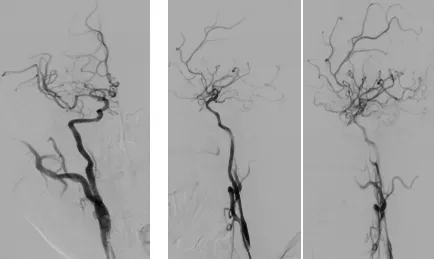

汉中市中心医院曹来伟主治医师接诊后考虑急性脑梗死,30分钟内,陪同患者完成头颅磁共振评估,提示右侧颈内动脉起始处闭塞,右侧大脑半球急性梗死。汉中市中心医院高级卒中中心团队在李定安主任带领下,迅速到达病房,从病史、查体、影像等多方面审慎分析,研判病情,共同制定了紧急救治方案,患者需要立即进行血管内取栓手术,如果不及时开通血管,将导致终身瘫痪卧床,甚至死亡。同患者随行人员详细交代病情,与家属电话沟通后,一致同意立即行机械取栓手术。

由于取栓手术必须在放射线透视下完成,术者要穿着十几斤重的铅衣,薛延华副主任医师、王衡副主任医师经过40余分钟紧张的手术,成功地再通了堵塞的血管,并置入颈动脉支架。术后,患者被送入神经内科监护室观察,第二天左侧肢体瘫痪就逐渐恢复正常,言语流利。术后复查头颅CT未见出血,经过5天精心的治疗和护理,出院时患者左侧肢体肌力恢复正常,取得了良好的治疗效果。家属非常感激,并送来锦旗及感谢信。